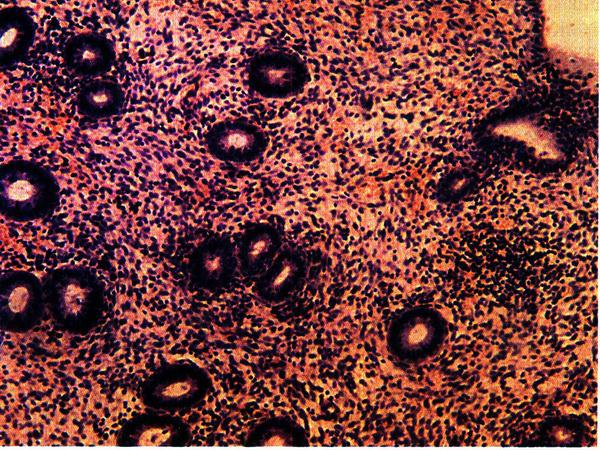

Фаза пролиферации (соответствует фолликулярной фазе в яичниках) продолжается в среднем 12–14 дней, начиная с 5–го дня цикла. В этот период образуется новый поверхностный слой с вытянутыми трубчатыми железами, выстланными цилиндрическим эпителием с повышенной митотической активностью. Толщина функционального слоя эндометрия составляет 8 мм (рис. 2.7).

Фаза секреции (лютеиновая фаза в яичниках) связана с активностью желтого тела, длится 14±1 день. В этот период эпителий желез эндометрия начинает вырабатывать секрет, содержащий кислые гликозаминогликаны, гликопротеиды, гликоген (рис. 2.8).

Рис. 2.7. Эндометрий в фазе пролиферации (средняя стадия). Окраска гематоксилином и эозином, х 200. Фото О.В. Зайратьянца

Рис. 2.8. Эндометрий в фазе секреции (средняя стадия). Окраска гематоксилином и эозином, х 200. Фото О.В. Зайратьянца